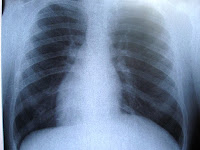

Friday’s MAPOC Complex Care Committee included a presentation on the cut to radiologists’ rates this last session. Representatives of the Radiological Society of Connecticut outlined the across-the-board cuts effective last April that dropped payments for interpreting images from 100% to 57.5% of Medicare rates, lower than rates paid by other states. The physicians are concerned that the cuts will impact Medicaid members’ access. Many private offices are no longer able to accept Medicaid patients who are shifted to hospitals which are paid higher rates than community providers. The presenters predicted that the state may not realize any savings, and consumers will have fewer options for care. Cuts were proposed to many specialty rates last year; all but radiologists were restored in the final budget. DSS stated that imaging rates are in line with other specialties, with other states, and that the state budget is very tight and cuts were necessary.